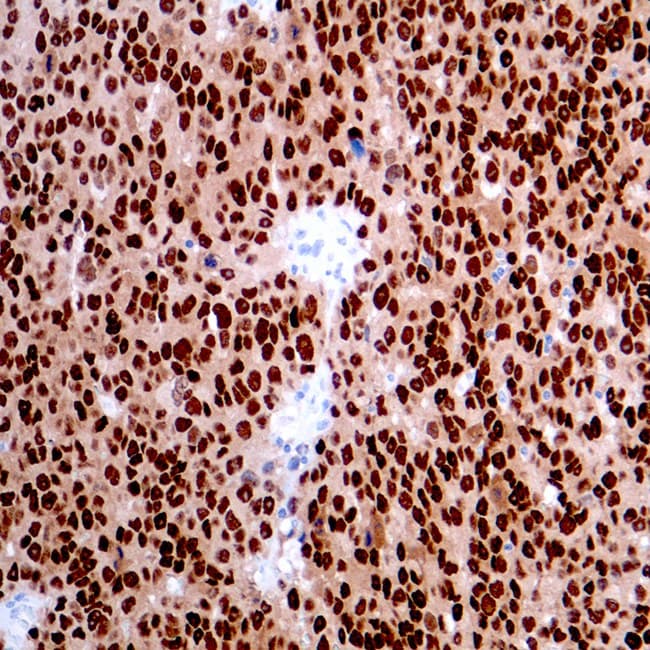

SRY (Sex Determining Region Y)-Box 10 (SOX-10), también conocido como factor de transcripción SOX-10, es un factor de transcripción nuclear que actúa en la regulación del desarrollo embrionario y en la especificación y diferenciación de las células de linaje melanocítico. Durante el desarrollo, SOX10 aparece por primera vez en la cresta neural en formación y continúa expresándose en las células de Schwann. Es importante para la diferenciación, maduración y mantenimiento de las células de Schwann y los melanocitos. SOX-10 se expresa de forma difusa en neurofibromas y schwannomas, y las mutaciones en el gen SOX-10 están relacionadas con las enfermedades de Waardenburg-Shah y Waardenburg-Hirschsprung. También se detecta en melanocitos y células epiteliales de glándulas salivales y mamarias. Los antiSOX-10 han demostrado ser sensibles al melanoma convencional, fusiforme y desmoplásico, y se han utilizado para detectar el melanoma metastásico y el nevus capsular ganglionar en los ganglios linfáticos centinela.

Sección de melanoma